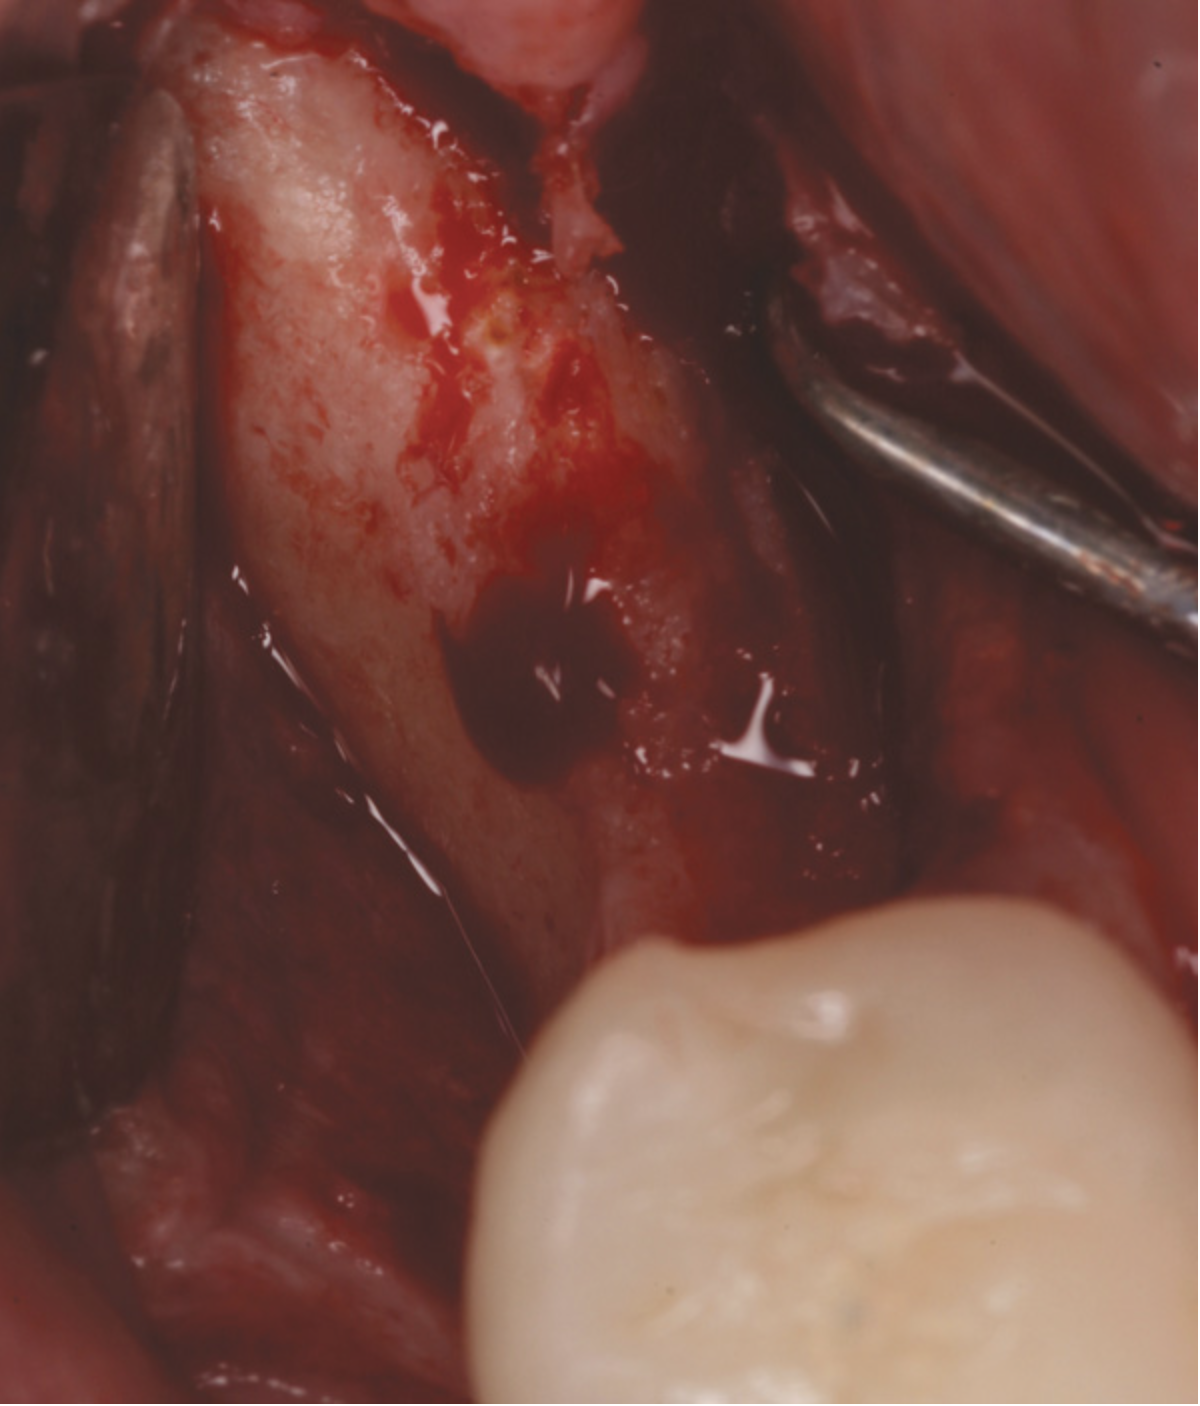

There are concerns that graft materials that fully resorb in a short timeframe may contribute to site collapse. Pure-phase beta-tricalcium phosphate (ß-TCP) (Figure 4) was one of the materials developed to address this concern. In a clinical and histologic study, extraction sockets were shown to have 91% of ridge width preserved when grafted with ß-TCP (Cerasorb®, Curasan, Inc., www.curasaninc.com) and covered with either a collagen or dense PTFE barrier.7 Dental implants were placed in these patients at 4 to 6 months postoperatively, a later time period than in the calcium sulfate studies. The patient shown in Figure 4 had only three maxillary teeth remaining, supporting an ill-fitting removable prosthesis. Due to the significant occlusal forces that were to be demanded on this single-tooth, implant-supported restoration, it was deemed advantageous to maximize the amount of vital bone in the recipient site. The area was left to heal for 7 months before flap exposure (Figure 5), implant placement in an ideal location, and graft analysis in the largest part of the defect. Analysis of the retrieved specimen showed 85% vital bone in the apical 90% of the core and a thin layer of nonresorbed ß-TCP at the crestal portion (Figure 6).

Fig 5. Reentry at 7 months demonstrated full ridge width preservation and minimal residual graft material.

Figure 5